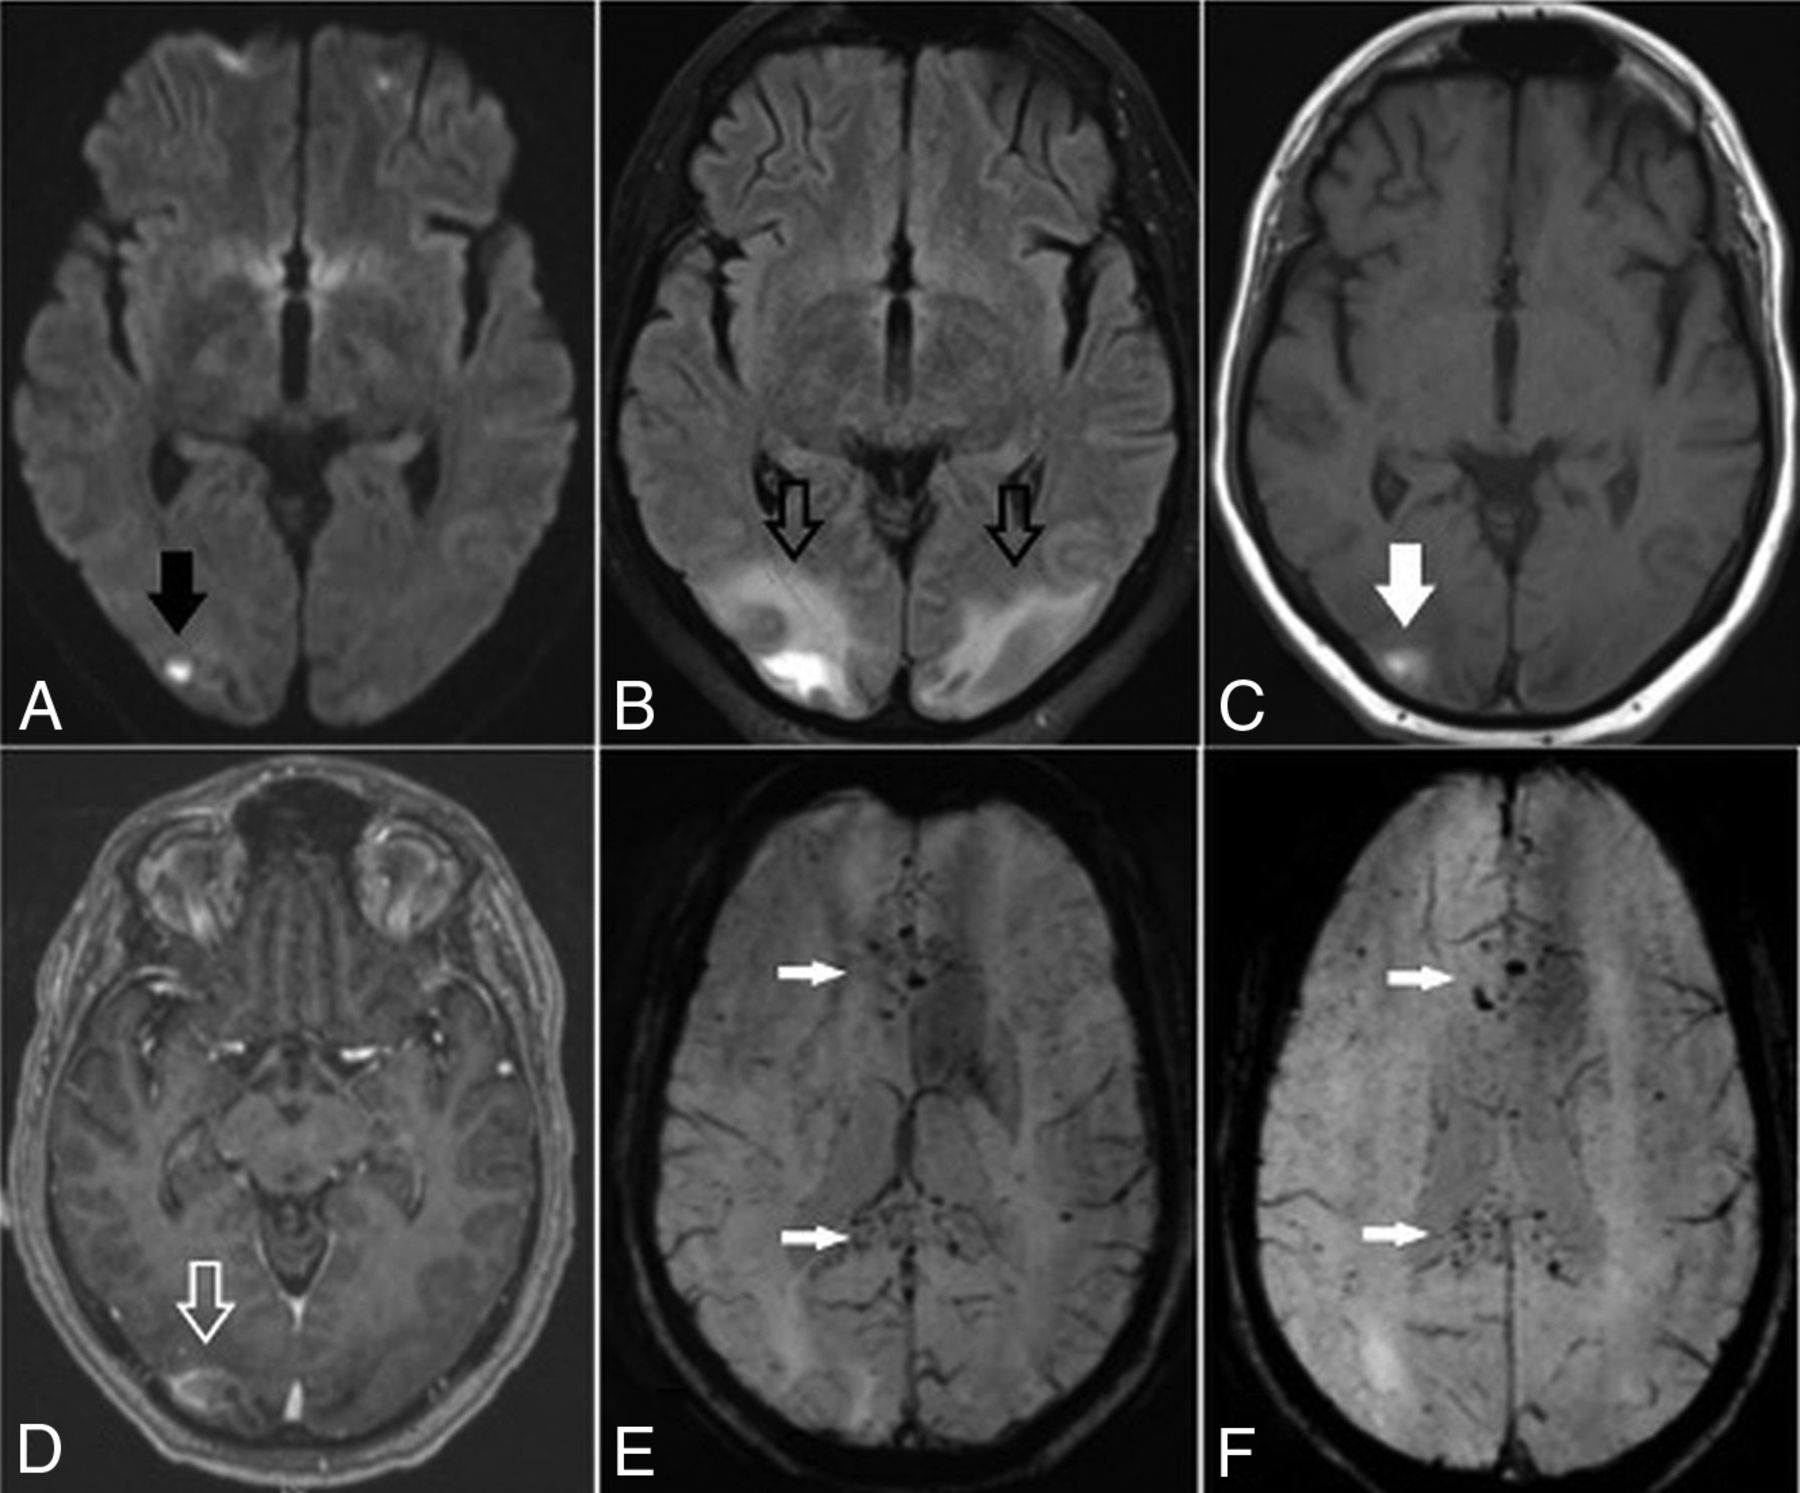

He subsequently developed fever and cough on March 17, had polymerase chain reaction testing positive for SARS-CoV-2, and was admitted into a local hospital for medical care. Two days later, the fever progressed to 105°F and he developed difficulty breathing and was transferred to a tertiary medical center for intensive care unit care and was placed on mechanical ventilation. On March 25, he developed shock with widely varying blood pressures from 70/30 to 180/90 mm Hg during his intensive care stay. On April 4, he was diagnosed with inflammatory cytokine release syndrome (high D-dimer, lactate dehydrogenase, C-reactive protein, and ferritin values) and developed an altered mental status. Noncontrast CT of the head was obtained and demonstrated focal vasogenic/cytotoxic edema in the posterior parieto-occipital regions bilaterally, which was subcortical in distribution, with a small right-sided hemorrhage (Fig 1); concurrently obtained CT venogram findings were normal. The patient was extubated and transferred to a medical floor on April 10, with gradual improvement in his mental status. MR imaging of the brain was performed on April 13 and confirmed vasogenic edema in the posterior parieto-occipital regions with subacute blood products suggestive of hemorrhagic posterior reversible encephalopathy syndrome (PRES). SWI revealed extensive petechial hemorrhages diffusely distributed throughout the corpus callosum (Fig 2).

Brain axial DWI (A), FLAIR (B), precontrast T1-weighted (C), postcontrast T1-weighted (D), and susceptibility-weighted (E and F) images obtained 8 days after CT demonstrate a small infarct in the right occipital region (arrow, A), persistent edema in the posterior parieto-occipital regions (hollow black arrows, B), subacute blood products in the location of the infarction (solid white arrow, C), and some contrast enhancement (hollow white arrow, D). There are diffuse petechial hemorrhages on SWI throughout the corpus callosum (white arrows, E and F).